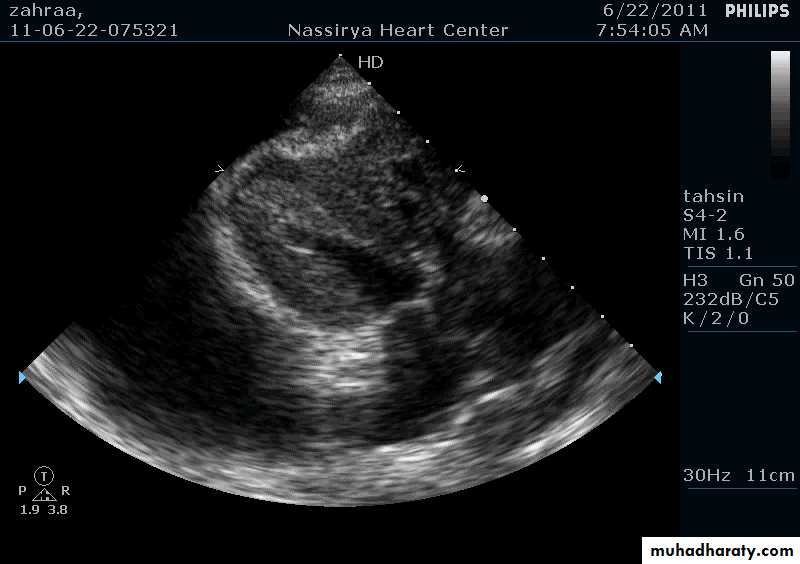

Pericardial Effusion: Investigation

Echocardiography: establishes the diagnosis31

Echocardiography & Doppler:RA & LA enlargement

Normal size ventricles

Pericardial thickening